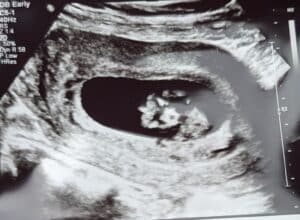

Ten Weeks Along With Our Baby Blessing!

Ten Weeks Along!

10-weeks-along-tubal-reversal-harris-pennsylvaniaWe are super excited!

Ten weeks along and got to see our little blessing all thanks to Dr. Monteith and team!

Patient age: 34

Tubal ligation type: Coagulation (burned)

Patient hometown: Harrisville, Pennsylvania